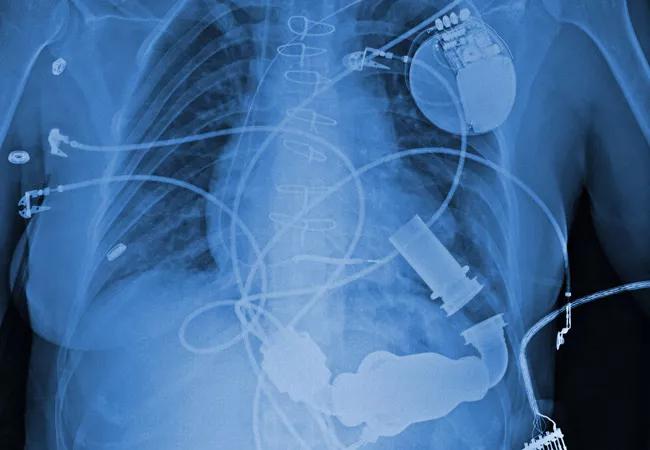

Implanted LVAD

The majority of left ventricular assist device (LVAD) implantations have been performed in advanced heart failure patients who are hospitalized and dependent on intravenous inotropic drugs. But what if the option of earlier LVAD placement were offered to patients who weren’t yet inotrope-dependent but still met clinical guidelines for LVAD implantation?